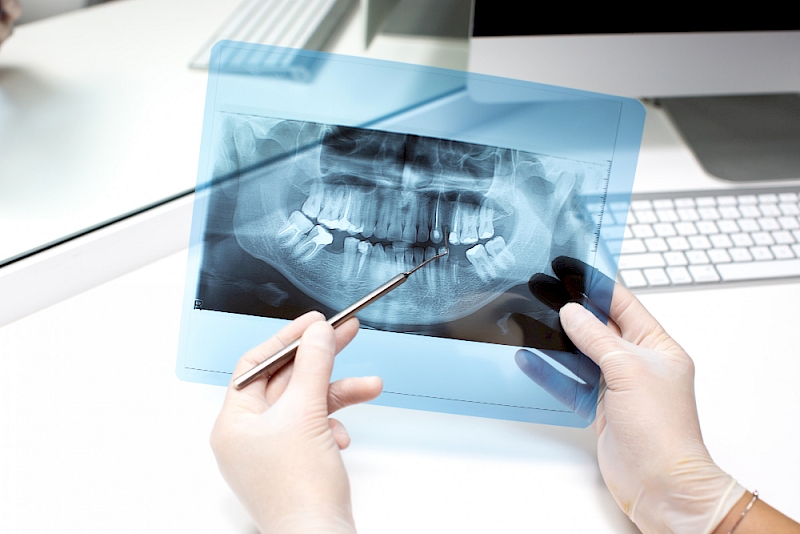

Dental Radiology and Imaging

The use of imaging methods during diagnosis, treatment plan and follow-up of treatment in oral and dental health is essential for success.

For this purpose, two-dimensional imaging radiographs and three-dimensional tomographs can be used.

Where Is Dental Radiology and Imaging Used?

- Detection of caries

- Before and during root canal treatment

- Detecting bone damage in cases with advanced gum disease

- Pre-implant surgery planning and follow-up of treatment

- In joint disorders

- In case of cysts and tumors related to teeth and bones

- Determining the position of the impacted tooth before surgical procedures

- In orthodontic treatment, in determining the relationship between the jaws and teeth and determining the treatment method.

- In the detection of salivary gland diseases

- Following the tooth development and growth of children

- In suspicion of tooth and jaw fracture